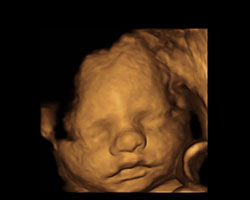

Em seguida mostramos-te um vídeo de um feto na 31ª semana, para que o possas ver em movimento. Também vais poder observar a sua evolução e desenvolvimento esta semana através de uma ecografia. Não percas!

Ecografia 31 semanas